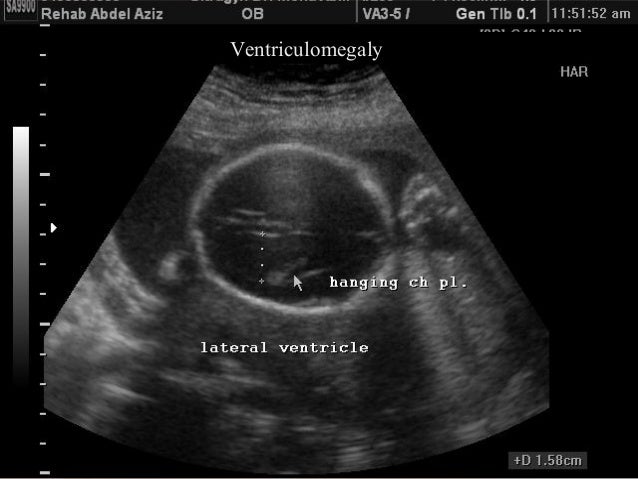

The anatomy scan is an essential level of scans which is also known as a level 2 ultrasound scan. The second trimester scan is a routine ultrasound examination in many countries that is primarily used to assess fetal anatomy and detect the presence of any fetal anomalies. Brain ventricles choroid plexus mid brain posterior fossa cerebellum cisterna magna.